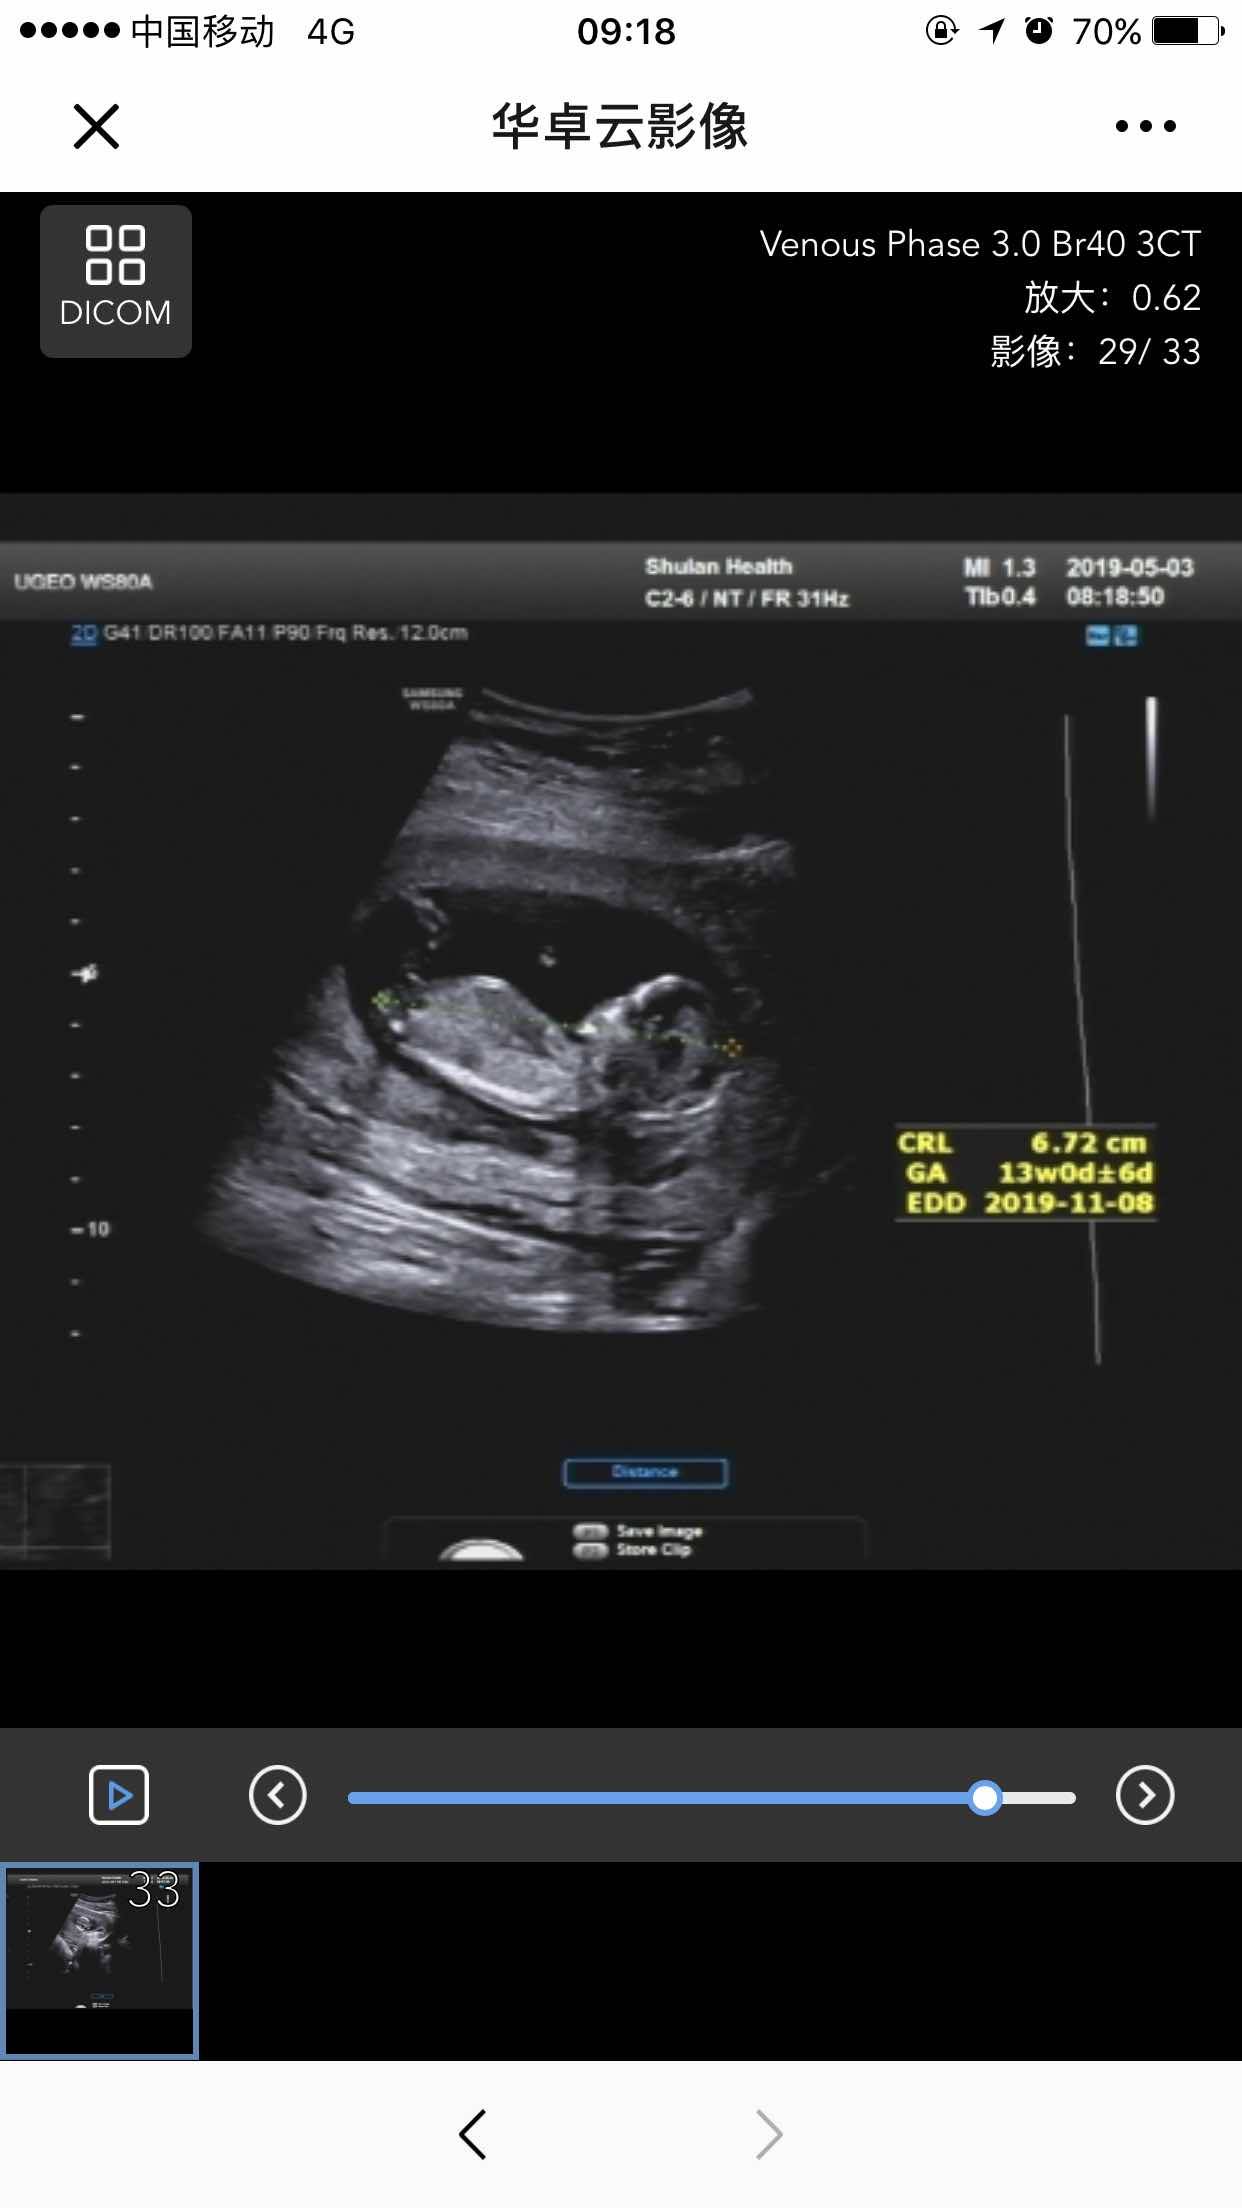

今天宝宝12W+6D了,去做了之前约好的NT,害怕宝宝不配合也害怕不好,总之各种担心,做的时候心跳的贼快,当妈了就是玻璃心,幸好一切顺利,然后去产科给医生看NT单子以及其他的检查单,顺便预约了22周的四维以及胎儿心脏彩超,果然怀孕就是一次次的打怪升级,不过只要结果是好的一切都值得。另外医生给我做胎心监测的时候说我胖太多了,让我控制饮食,一般产科早期让胖2kg,中期5kg,后期5kg,而我已经106斤了😂加上我是SLE,医生说我属于高危妊娠,下周去社区建卡,到时候把每次社区的检查单以及我每个月主治医师的检查单一起拿给她看,要动态监测,希望一切都能顺利,生个健康的宝宝😄